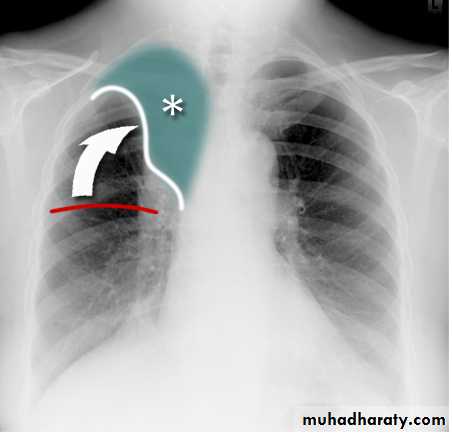

Pleural Effusion on Chest Radiographs.

Posteroanterior (A) and lateral (B) chest radiographs demonstrate the typical meniscoid appearance (arrows) in a patient with a left pleural effusion